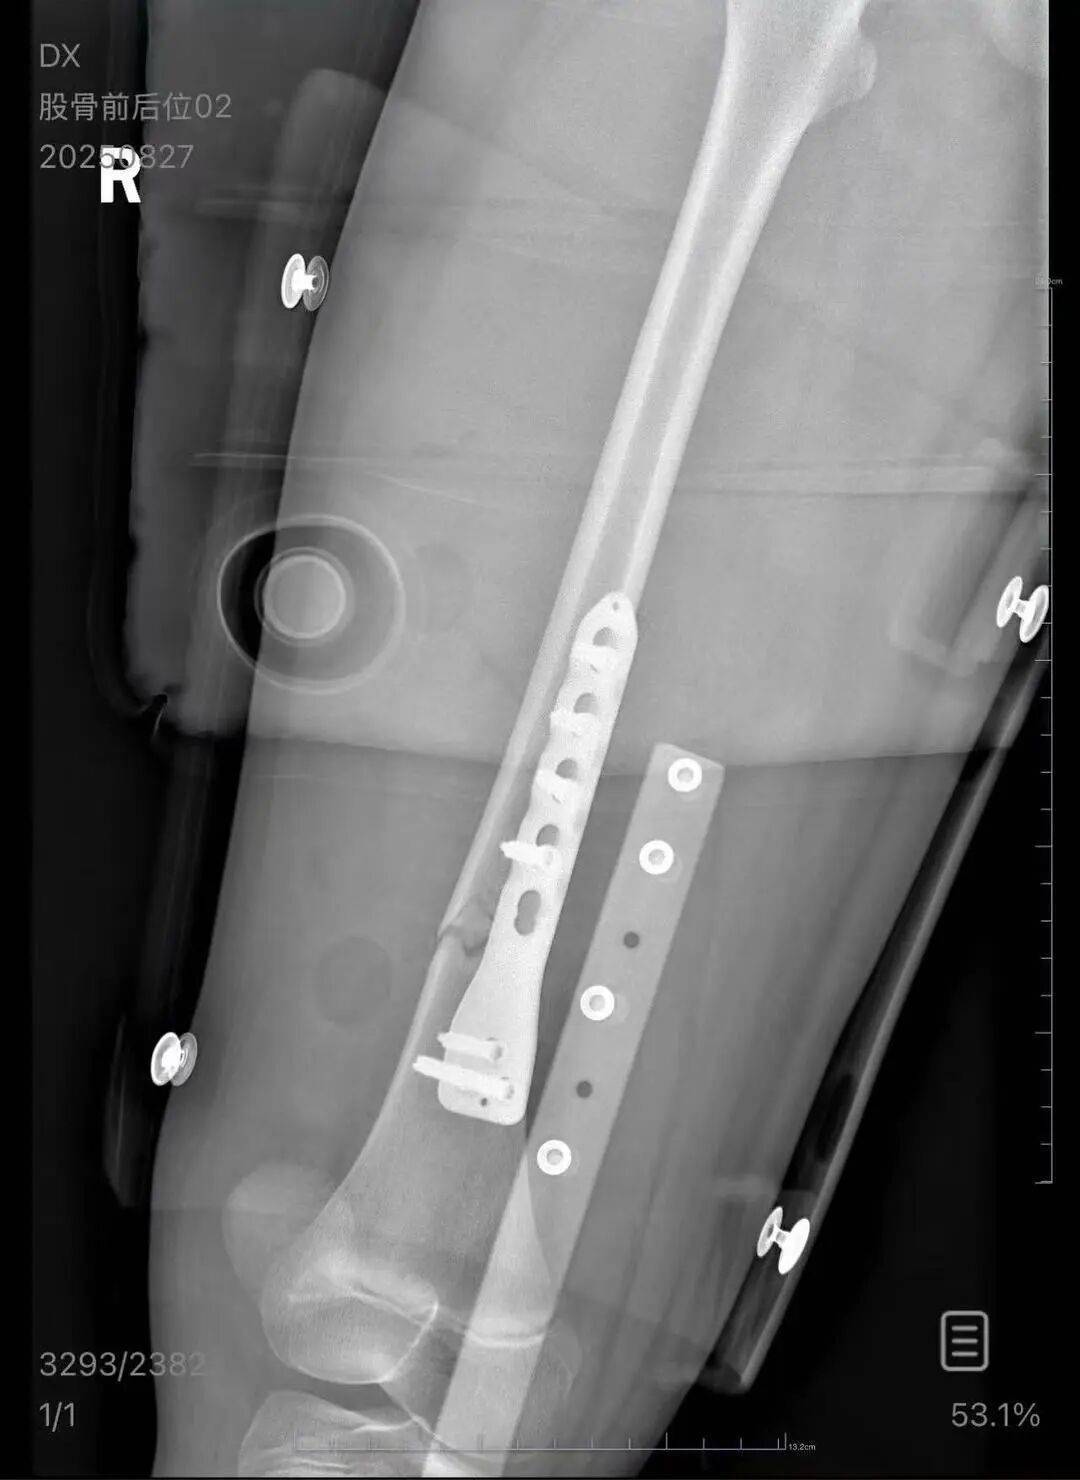

朱女士向记者出示的医院病历显示,8月24日凌晨,朱女士的女儿到医院就诊加密货币。医院诊断朱女士的女儿右股骨骨折,需要住院进一步治疗。

▲朱女士女儿手术后拍的X光片 受访者供图